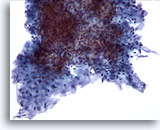

Figure 86

Salivary gland FNA, pleomorphic adenoma. At the central upper portion of the photo is an irregular grouping of epithelial cells with oval bland nuclei. Some have very tiny nucleoli. Immediately beneath this is stroma and a few single stromal cells. Pleomorphic adenoma is the most common salivary gland tumor. 40x

Salivary gland FNA, pleomorphic adenoma.

At the central upper portion of the photo is an irregular grouping of epithelial cells with oval bland nuclei. Some have very tiny nucleoli. Immediately beneath this is stroma and a few single stromal cells. Pleomorphic adenoma is the most common salivary gland tumor.

40x